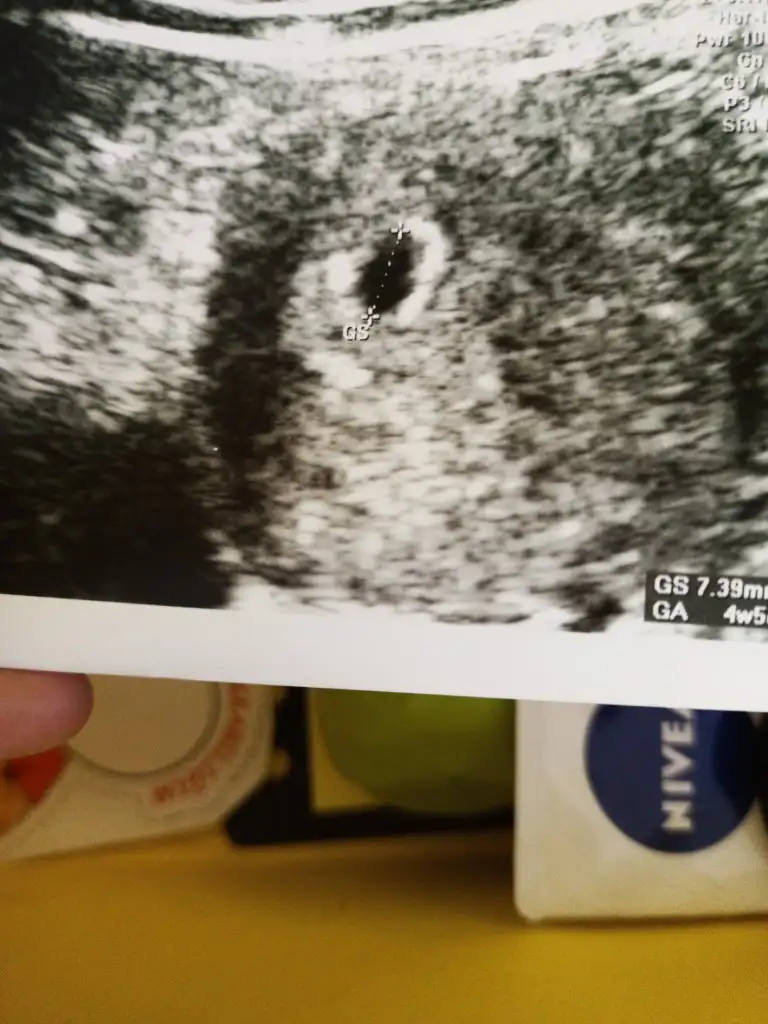

Kasım 12 de yumurtlama olması gerekirken olmadı 4 gün sonra oldu 16 kasım da şimdi hamileyim şu an haftalık hesabı 5 hafta oluyor tam ama yumurtlama 4 gün geç olduğu için ben 4 gün çıkarıp 4+3 gün diye mi düşünmeliyim?

Son adet tarihini dikkate alacaksınız. Ultrasonla uyumlu çıkacaktır merak etmeyin.